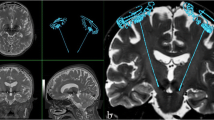

Borders of STN on both sequences were determined for each MER track by manually entering depth changes in relation to target depth into the planning software. Steps of 0.5 mm along the trajectory were used for border identification. Borders were defined as the value, given in mm in relation to target depth, for which the trajectory was situated inside the STN on axial and coronal images. The dorsal border was defined as the last slice where the trajectory was still in the hypointense nucleus before entering the dorsal white matter tracts. The ventral border was identified by determining the last slice on which the trajectory was located in the hypointense nucleus, without having entered the SN. The start of the SN was represented by an increased hypointense area ventromedial to the STN, when the posterolateral tail of the STN could no longer be identified on axial images. On both T2-weighted and SWI sequences, a small less hypodense area between the STN and SN was often visible on coronal images. We considered this area to be in between STN and SN. It was noted that the SN appeared more hypointense than the STN on both sequences. All trajectory borders and representation of STN at target depth were determined by two independent reviewers who were unaware of MER measurements (SB and LVM). In case of disagreement, images were reviewed again and borders were determined after consensus was reached. To prevent bias in retrospective data collection, MRI-STN borders for each track were determined before review of MER-STN borders. We compared delineation of STN defined by MER, which we took as the golden standard, with the STN delineated on both MRI sequences. Figure 1 illustrates MRI-STN border determination.

Delineation of the ventral MRI-STN border. Illustration of ventral MRI-STN border delineation along a MER track. The MER track is projected on a 3-T SWI scan. Both axial (top) and coronal (bottom) planes are visualized. The targeting dot, indicated by the arrow, represents the tip of the ME. The planning software is used to extrapolate the track past target depth by manually entering values into planning software, 3 mm past target in this illustration. On the axial image, the tip of the ME is inside the subthalamic nucleus (STN), on the border between the more anteromedially located substantia nigra (SN) and at the level of the anterior border of the red nucleus (RN). On the coronal image, the two parallel lines illustrate the ‘channel’ between the STN and the SN. We considered the most lateral aspect of this the ventral STN border. In this case, 3 mm past target